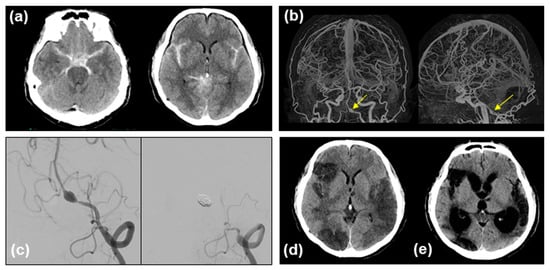

2.2. Contracting Case without Vasospasm

2.3. Clot Density Measurements